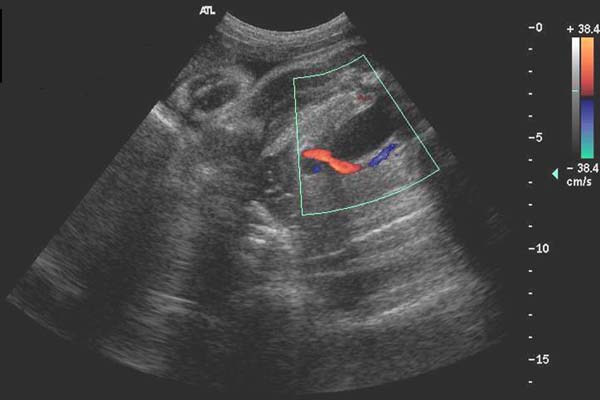

Artère ombilicale unique